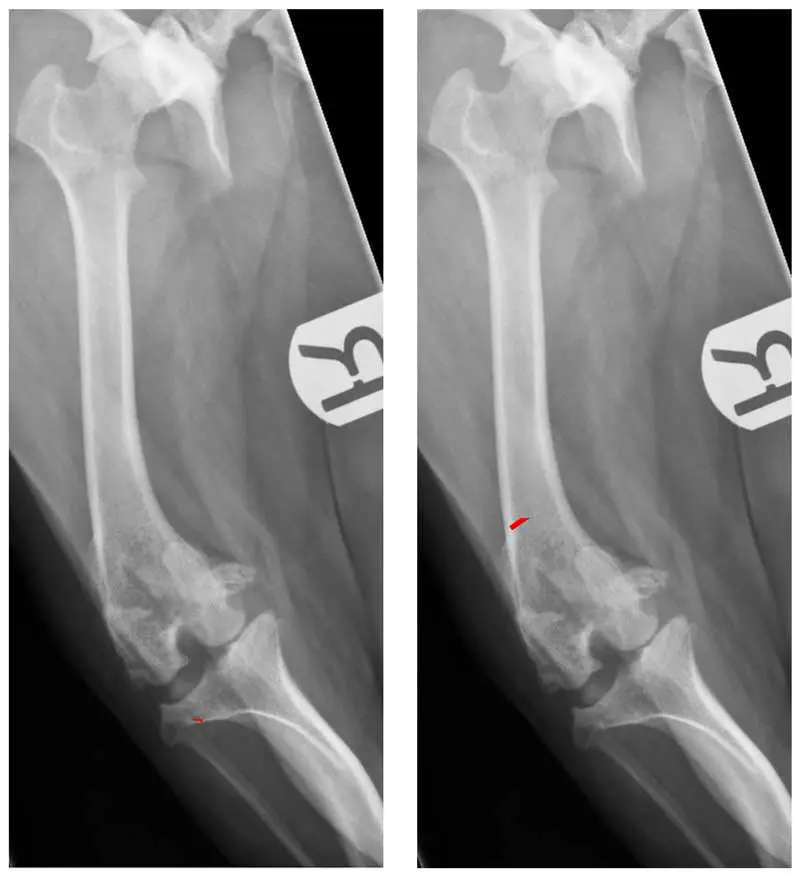

Tibial tuberosity transposition: a powerful but limited tool

TTT aims to realign the quadriceps mechanism by repositioning the patellar tendon insertion (Figure 2). TTT can be highly effective. It is also worth noting, however, that most dogs with lower-grade PL do not have a medially positioned tibial tuberosity (Yasukawa et al, 2016), so TTT is not truly addressing a deformity (medial tibial tuberosity), but is actually causing one (lateral tibial tuberosity). This is not inherently problematic, provided it is performed within its biomechanical limits. TTT can compensate for deformities including femoral varus, femoral torsion and stifle joint rotation to a point.

Failure to address these deformities specifically may risk creating excessive stresses at the tibial tuberosity osteotomy site, contributing to complications such as avulsion or delayed union (Arthurs and Langley-Hobbs, 2006). Additionally, it could be argued that compensation for femoral or stifle deformities with TTT could mean continued non-parallelism between the trochlear groove and the direction of tracking of the patella.

TTT should be regarded as a component of alignment correction, not a substitute for addressing femoral geometry when significant deformity exists. It is reasonably considered the mainstay procedure for PL surgery.